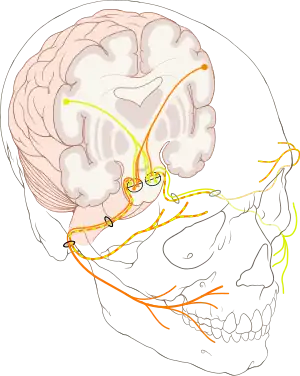

The course of the facial nerve is shown here | |

The facial nerve, also known as the seventh cranial nerve, cranial nerve VII, or simply CN VII, is a cranial nerve that emerges from the pons of the brainstem, controls the muscles of facial expression, and functions in the conveyance of taste sensations from the anterior two-thirds of the tongue.[1][2] The nerve typically travels from the pons through the facial canal in the temporal bone and exits the skull at the stylomastoid foramen.[3] It arises from the brainstem from an area posterior to the cranial nerve VI (abducens nerve) and anterior to cranial nerve VIII (vestibulocochlear nerve).

The path of the facial nerve can be divided into six segments:

- intracranial (cisternal) segment (from brainstem pons to internal auditory canal)

- meatal (canalicular) segment (within the internal auditory canal)

- labyrinthine segment (internal auditory canal to geniculate ganglion)

- tympanic (or horizontal) segment (from geniculate ganglion to pyramidal eminence)

- mastoid (or vertical) segment (from pyramidal eminence to stylomastoid foramen)

- extratemporal segment (from stylomastoid foramen to post parotid branches)

The motor part of the facial nerve arises from the facial nerve nucleus in the pons, while the sensory and parasympathetic parts of the facial nerve arise from the intermediate nerve.

From the brain stem, the motor and sensory parts of the facial nerve join and traverse the posterior cranial fossa before entering the petrous temporal bone via the internal auditory meatus. Upon exiting the internal auditory meatus, the nerve then runs a tortuous course through the facial canal, which is divided into the labyrinthine, tympanic, and mastoid segments.